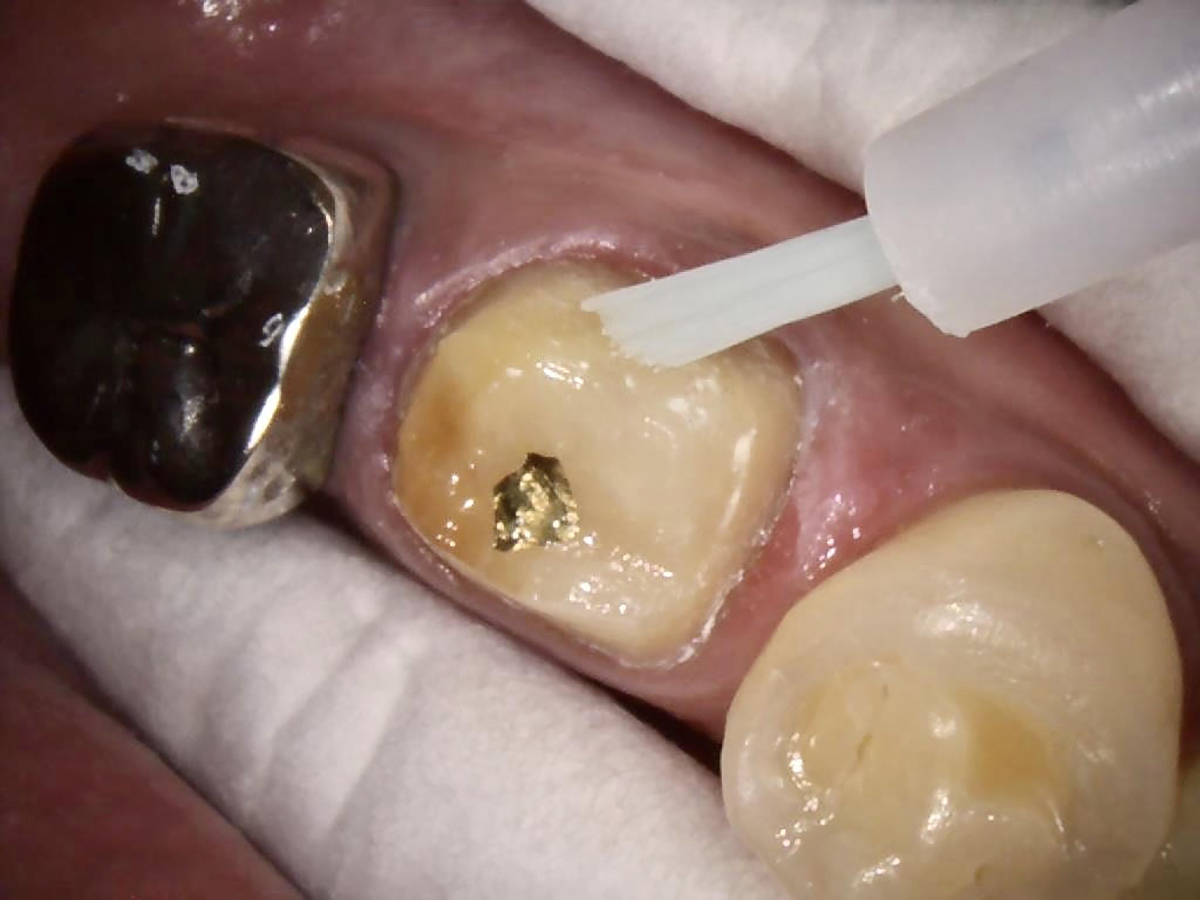

Fig 2. Tooth No. 30 after clean and neat cavity preparation.

Figure 2

After anesthetic with 2% lidocaine with 1:100,000 epinephrine, a rubber dam was placed. The existing amalgam was removed using an inverted cone diamond bur and a small round diamond bur. The photograph showed recurrent and mesial caries. Removal of all the soft caries was performed using carbide round burs with a slow-speed handpiece. To make a clean and neat cavity preparation, all the superficial caries and stains were removed conservatively with a small round diamond bur. Then an intraoral photograph was taken to ensure that no caries was left behind (Figure 2).